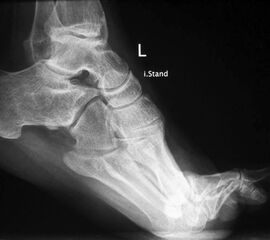

• Fuß belastet dp und seitlich (Abb. 14 und 15)

Typische Merkmale der Standard-Seitaufnahme des Fußes im Stand

• Knöchelgabel ist außen rotiert

• Talus und Calcaneus verlaufen fast parallel

• Sinus tarsi ist einsehbar

• Subtalare Gelenklinie verläuft horizontal und ist breit einsehbar

• Der Abstand Malleolus medialis zum Os naviculare ist verkürzt

• Der Calcaneus erscheint verkürzt

• Der Krümmungsscheitel des Fußes ist erhöht

• Calcaneus pitch ist meist erhöht, der Rückfuß Equinus ist eher selten 12